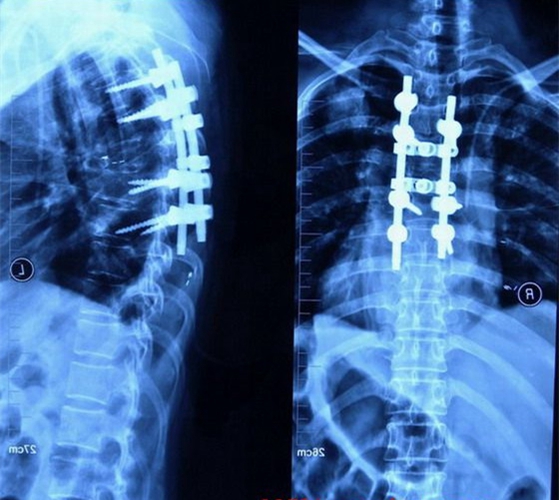

肺腺癌胸椎轉移瘤